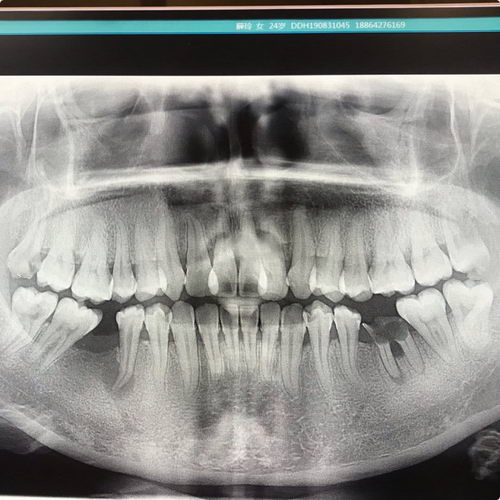

记录我在岳阳拔牙、种植、正畸、根管治疗的艰辛治牙道路!记录下自己的治牙之路,遗传我老爸的蛀牙基因,好像从小就一直蛀牙,但是一次牙医都没看过,今年25的我还是第一次看牙医,生完孩子后开始惜命了,本来是蛀牙掉了想去了解下种植牙,到岳阳华厦恒康医院拍片检查一下,这一检查不得了,一嘴的问题需要治疗,当场枯萎!下面说下我的口腔问题…

2.拔牙。片子里可以看到有一个烂到家的牙根,右上右下两颗智齿也蛀牙了,医生说需要拔5颗牙 ,1颗残根,4颗智齿,不拍片我都不知道自己有智齿。

3.根管治疗。左侧那个空也是因为蛀牙掉了的,旁边看似好好的一颗牙居然也坏了,牙根发炎需要根管,不然这颗牙也保不住了…根管完要加个全瓷牙冠保护起来。

4.正畸。拔掉两颗蛀虫的智齿以后,要把旁边这颗歪掉的大牙拉回去,不然缝隙太小,种牙效果不好。

5.种牙。我订了一颗瑞士诺贝尔…15000一颗,最好的一种,管的时间比较长,拔掉烂牙根以后恢复下就可以种了,左边那个空牙要等正畸做完再说种植的事了,医生说还需要植骨粉。